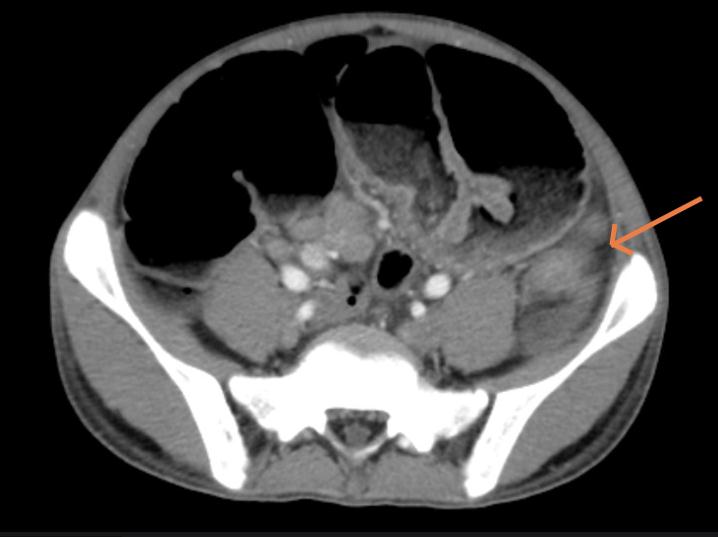

Cắt lớp vi tính ổ bụng: Các quai ruột non và khung đại tràng giãn lớn, đường kính lớn nhất 57mm, trong có mức dịch khí, vị trí chuyển tiếp là đoạn đại tràng trái, tại vị trí này, thành đại tràng dày nhẹ.

![]() |

Hình 1. Hình ảnh cắt lớp vi tính ổ bụng